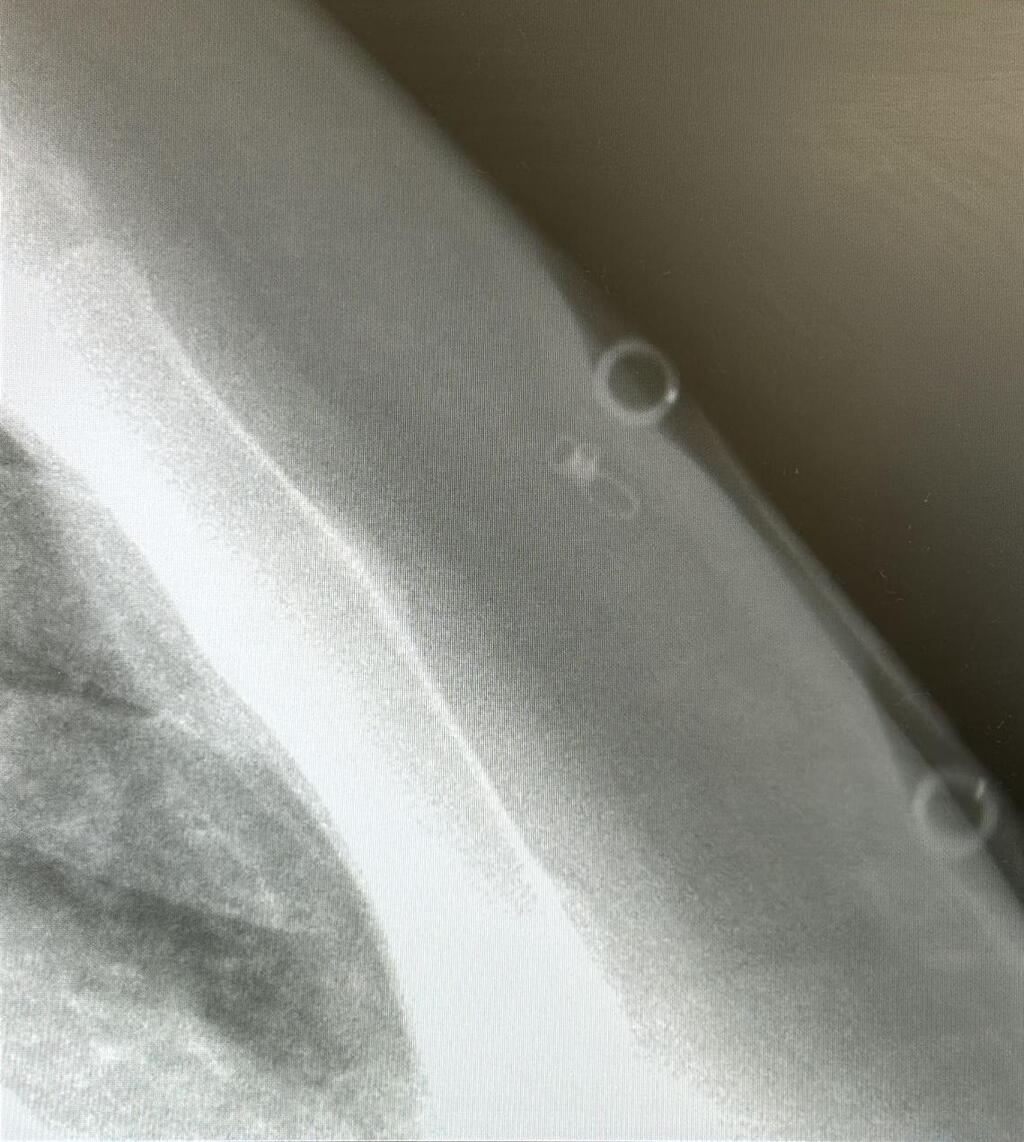

At the hospital, Krief was initially embarrassed but relieved to meet a doctor familiar with dermal piercings. “The first doctor I saw wore a dermal himself and knew exactly what to look for,” she explained. After an initial failed attempt to locate the implant, imaging and creative marking with probes pinpointed it, allowing surgeons to remove it under local anesthesia with a small incision, leaving four stitches.

Dr. Oren HanisPhoto: Meir Medical CenterDr. Oren Hanis and Dr. Hagai Soback from Meir Medical Center described the case: “The patient arrived with a dermal piercing complication where the implant was engulfed in her chest’s soft tissue.

"Locating the metal piece was challenging, but with imaging and minimal surgery, we extracted it.” Krief praised the team’s care, saying, “They worked creatively to avoid a large scar. I’m so grateful but people need to know this risk.”